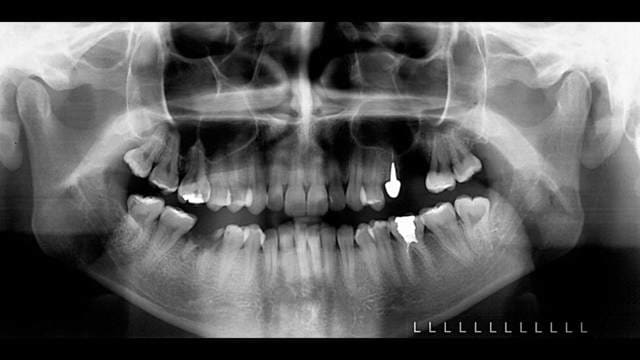

Cookie Consent byPrivacyPolicies.comInsertion immediate au niveau de 46 dans le septum - Eugenol

Insertion immediate au niveau de 46 dans le septum